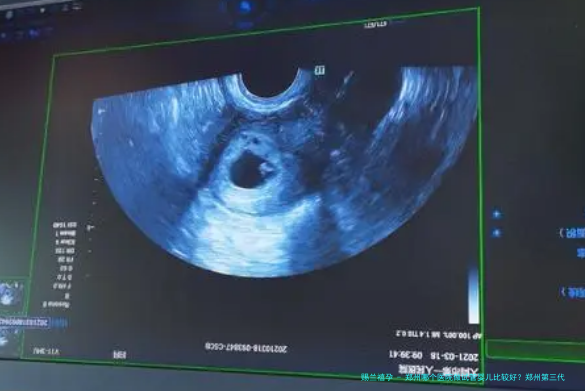

越来越多的夫妻有这样的情况。因何会出现试管助孕的问题?造成这种情况的因素无数,问题已经存在,继续担心没有任何寓意。所以要尽快找到专业的医院做手术,才能知道是否有做双亲的可能。要是我们想要知道道终归是怎么回事,可以瞧瞧下方关于郑州哪一家医院在做试管婴儿的最佳介绍。

现在很多夫妻都会在当地做试管手术,因为在国内试管水平已经很平衡了,不会有很大的差距,而且试管手术的费用也不算太低,所以不消出去做手术,除了更方便之外,还能省去许多的费用,自然也会成为还要多人的理想选择。人会越发注意郑州哪家医院有前沿可靠的试管技术。妇幼健康医院、郑达大学第一所属医院、助孕医院、郑州大学第二所属医院等。都值得的多认识。

为了成功,试管操作需要满足更多的条件。除此之外,还会受到很多因素的影响。从这些方面可以知道试管失败率真的很高,郑州哪一家医院做试管婴儿相较好?我已经讲过一些技术先进的有名气医院,所以当然要看如何才能有更高的成功率。不管是哪家医院,只要年龄越小,身体素质越好,卵子质量越高,就越容易成功。

现在试管技术有了更大的进步。要是要么选择第一代或者第二代技术,会出现一些不可避免的问题,固然对于伙伴来说也不是一个理想的抉择。要是能尝试三代手术,信赖大家都会更放心。上述提到的医院都把握了三代技术,朋友可以多查询。

知道了这一点,郑州哪一家医院做试管婴儿相较好?以及第三代技术,仔细看过介绍的朋友可以知道答案是什么。第三代更受欢迎的原因是,它可以确保试管婴儿更健康,并且可以检测出患有遗传病的基因。当然也有很多优点。